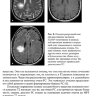

Рассмотрены разнообразные новые подходы к лечению, часть из которых уже внедряется в повседневную практику. Представлены результаты наиболее значимых международных исследований последних лет. В данное издание нами включена также глава, посвященная рассеянному склерозу у детей и его дифференциальной диагностике. Увеличено число иллюстраций - авторы выражают благодарность сотрудникам отделения нейрорентгенологии Национального медицинского исследовательского центра нейрохирургии им. Н. Н. Бурденко - академику РАН, д.м.н. В. Н. Корниенко, академику РАН, д.м.н., проф. И. Н. Пронину, к.м.н. С. В. Серкову - и заведующей отделением лучевой диагностики клиники нервных болезней Первого МГМУ им. И. М. Сеченова к.м.н. Е. В. Шашковой за предоставленные магнитно-резонансные томограммы, а также д.м.н. Г. Г. Торопиной за иллюстрацию изменений вызванных потенциалов при рассеянном склерозе.

3.1. Нейровизуализационные методы обследования